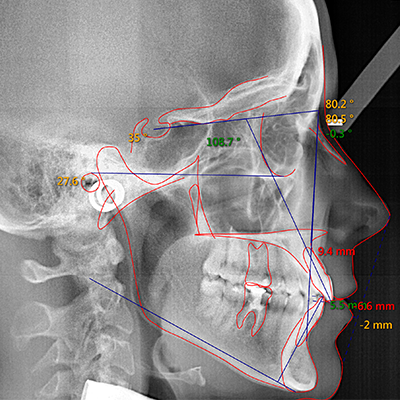

At Greenwich Braces, we offer the highest level of x-ray technology to provide the most effective care to our patients. All of our x-rays are digital, in order to ensure the least dose of radiation possible with the most accurate image. Additionally, our radiographic unit allows us to customize exposure values based on patient size, further minimizing the radiation dose. Finally, we utilize the safest radiation techniques, protecting both our patients and staff.